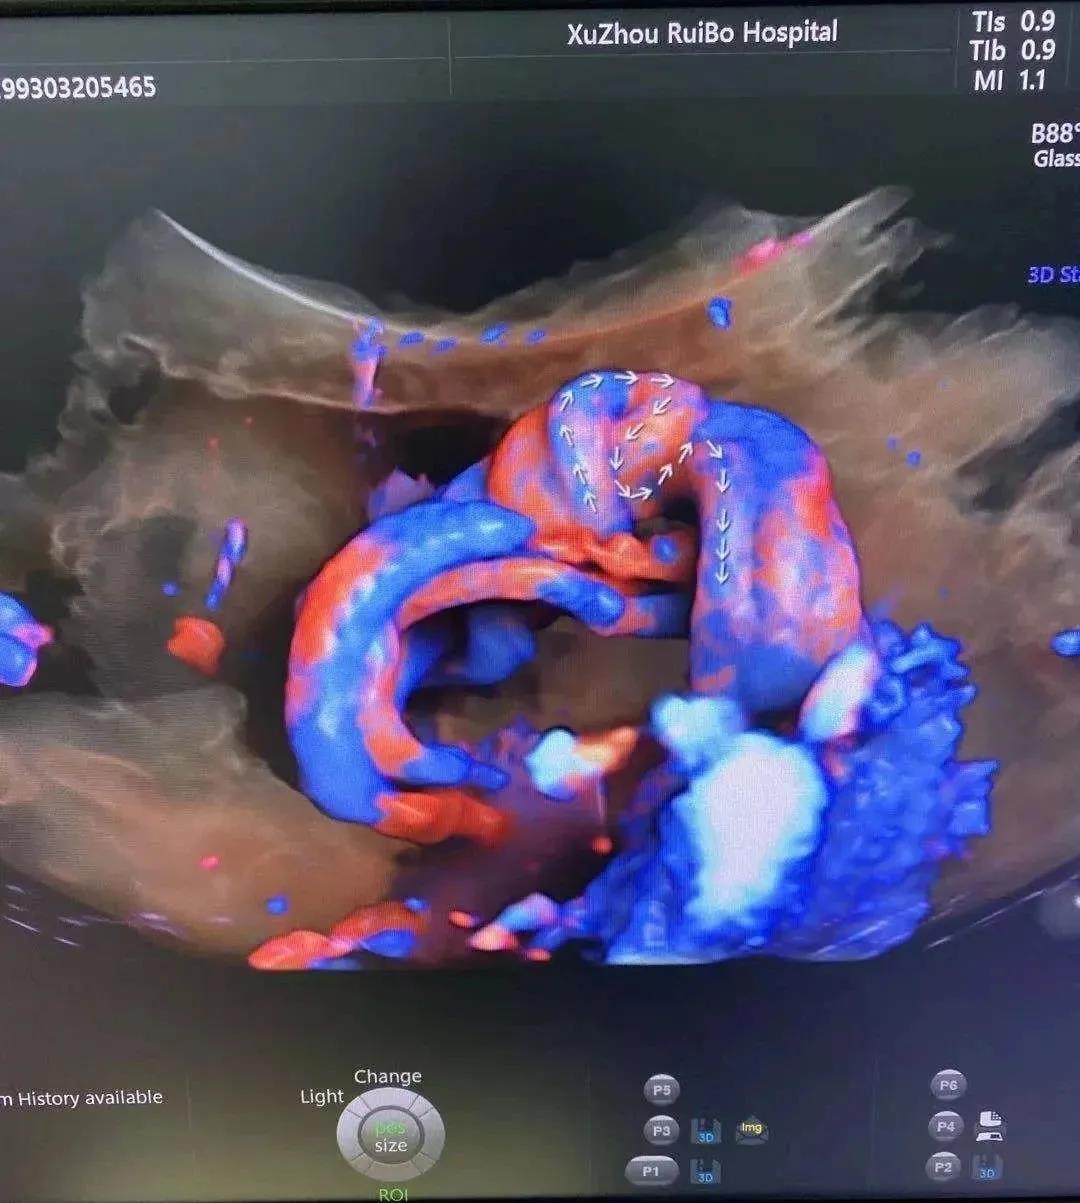

邓女士宝宝脐带真结+脐带扭转40圈实拍

就是这个淘气的小王子,将脐带打了个真结,还足足扭转了整整40圈,着实让大家捏了一把汗啊!

邓女士宝宝脐带真结+脐带扭转40圈实拍“当时真的是挺危急的,但是在李风院长带领的团队,密切的配合下,我们母子俩的生命安全被他们守护住了!在这个医患关系如此紧张的时代里,我有幸遇到这样有爱的医护团队,真的是太幸运了!”邓女士欣慰的说道。